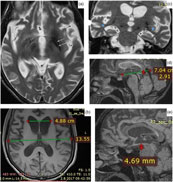

The brain magnetic resonance imaging (MRI) revealed bilateral hypointensities in globus pallidus and substantia nigra, mild brain atrophy and enlargement in temporal horns of lateral ventricles (Figure 2). Medullary lamina was prominent specifically on the left side on T2-weighted MRI. Evans index was 0.35, suggesting hydrocephalus. Mamillopontine distance was decreased, measured as 4.7 millimeters (mm). Spleniochiasmal distance was decreased, measured as −2.9 mm.

Figure 2: Magnetic resonance imaging findings. (a) Prominent medullary lamina specifically on the left side. (b) Calculation of Evan's index. (c) Enlargement in lateral ventricle temporal horns (blue arrows). (d) Calculation of mamillopontin distance. (e) Calculation of spleniochiasmal distance.

Hartig et al.Reference Hartig, Iuso and Haack 1 and Olgiati et al.Reference Olgiati, Doğu and Tufekcioglu 3 observed bilateral hypointensities in globus pallidus and substantia nigra on T2- or susceptibility-weighted MRI images in their case series. Olgiati et al.Reference Olgiati, Doğu and Tufekcioglu 3 reported that the hyperintensity of the medial medullary lamina between the internal and external parts of globus pallidus was also commonly observed. Additionally, we report hydrocephalus in MRI. This is a new imaging finding which has not been previously reported in MPAN. Although the patient had brain atrophy, the Evans index being over 0.30, the enlargement of the lateral ventricle temporal horns, increased frontal horn radius, increased third ventricle diameter, mild enlargement of third ventricle recesses, cingulate sulcus sign, and decreased mamillopontine diameter suggest hydrocephalus over atrophy.